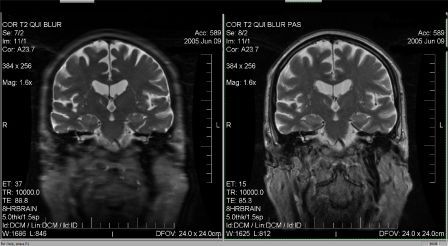

Tu as raison de préciser Higgins que ce n'est pas l'artéfact de troncature... Cet artéfact est dû à une trop grande différence de pondération entre le TE effectif (TE eff) qui va coder pour les lignes centrales de l'espace de Fourier et la pondération du dernier écho du train d'échos (TE max) qui lui, va coder les lignes périphériques de l'espace K. Dans l'exemple ci-dessous, vous pouvez trouver une image volontairement mal paramétrée pour créer du blurring (Train d'écho trop grand) et une image optimisée (paramètres réglés pour que le TE effectif soit au centre du train d'échos). Cet artéfact est souvent confondu avec l'artéfact de mouvement ou est souvent pris pour une mauvaise résolution spatiale...

Pièces jointes : |

blurring anonyme.jpg [ 25.21 Kio | Consulté 49968 fois ]